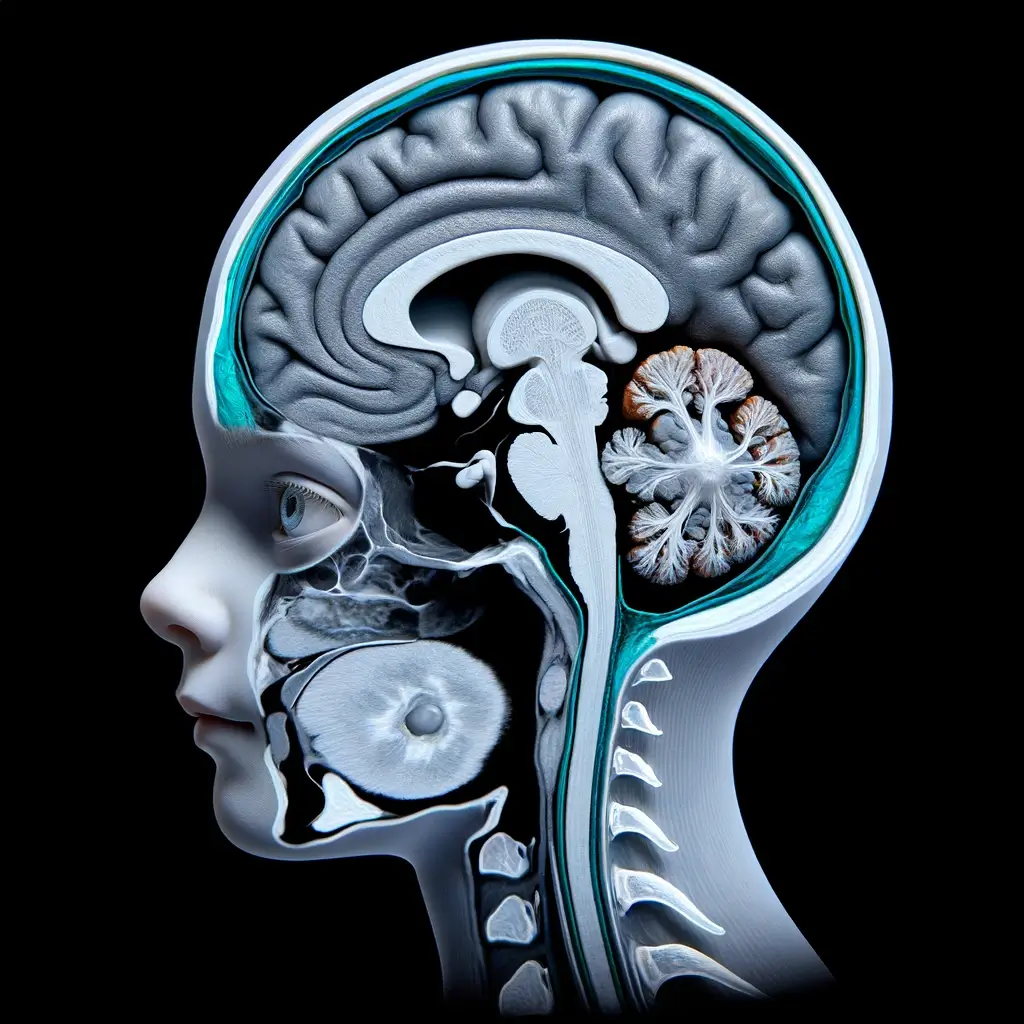

주요 특징으로는 제4뇌실의 확장 및 소뇌 발달 부전이 있으며, 제4뇌실의 출구가 부분적 또는 완전히 막혀 있어 뇌척수액의 흐름이 차단되고, 이로 인해 제4뇌실이 확장됩니다. 이러한 소뇌의 발달 부전은 운동 능력의 결핍으로 이어집니다.

- 컴퓨터단층촬영(CT) : X-ray를 이용해 몸 내부의 구조를 3차원적으로 보여주며, 물뇌증 진단과 댄디워커증후군 평가에 도움을 줍니다.

- 자기공명영상(MRI) 촬영 : 강력한 자기장을 이용해 몸의 내부 구조를 상세하게 보여주며, 엑스레이를 사용하지 않습니다.